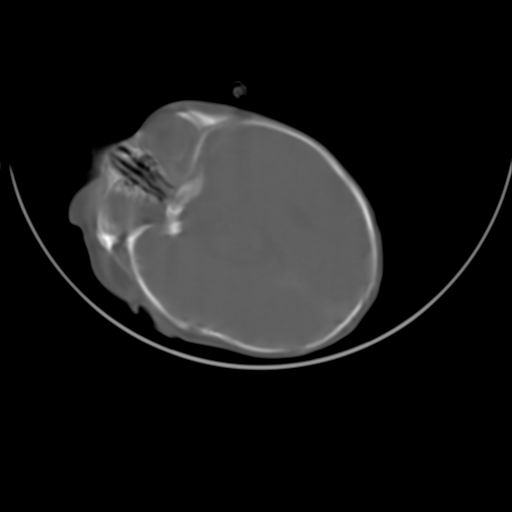

双侧硬膜下血肿并蛛网膜下腔出血。

双侧硬膜下血肿并蛛网膜下腔出血

硬膜下及蛛网膜下腔出血。

hie 蛛网膜下腔出血,硬膜下血肿。

hie;双侧硬膜下血肿并蛛网膜下腔出血

hie,双侧硬膜下血肿并蛛网膜下腔出血

双侧硬膜下血肿并蛛网膜下腔出血,考虑维生素k缺乏引起.

较大范围出血,应考虑维生素k缺乏引起,结合临床吧。

好像脑实质没有明显低密度影,各位大侠怎么支持hie呢?